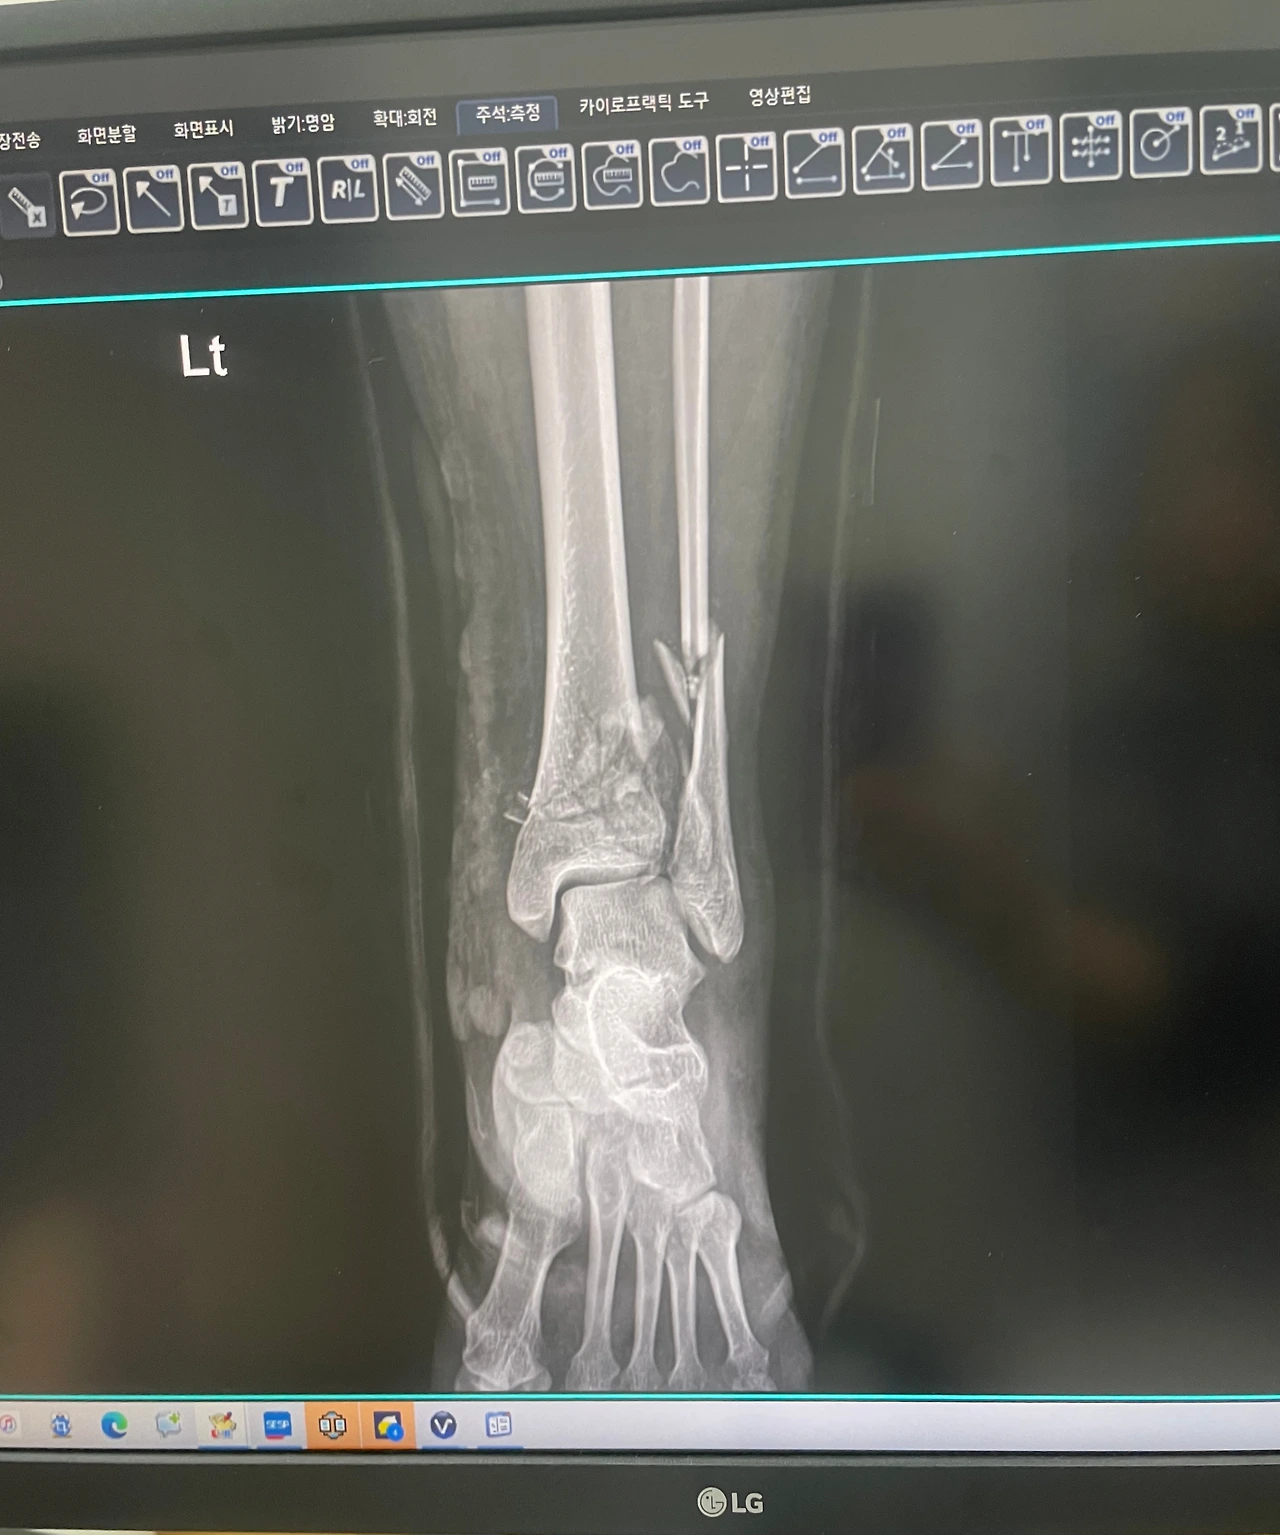

지난 5월에 한국의 제주도에 여행을 가서 사진을 찍으려다 아차 하는 순간에 낙상하고 왼쪽 발목이 부러지는 사고를 경험했다. 생각보다 뼈가 심해서 부러져서 철심을 3개를 넣어서 나사로 하나하나 다 잇는 대수술을 받게 되었다. 사고당해서 정신없었지만 수술 후 한국에서는 빨리 퇴원을 시켜주지 않아서 부득이 2주 넘게 한국에 입원하며 치료해야 하는 시간 속에 있었다.

이제 왼쪽 발목뼈가 많이 붙었는지 왼발을 디뎌도 통증이 없어지고 있다. 아직 두 발로 걷기는 무리지만 목발을 짚고 걸을 수 있기에 나 혼자 기특해한다.